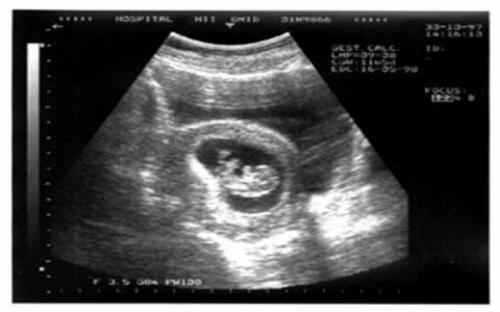

В январе 2009 года в больницу китайского города Хуангиаотан обратилась 92-летняя местная жительница Хуан Юиджун. Пожилая женщина жаловалась на очень сильные боли в желудке.

Медики же, к своему удивлению, выяснили, что престарелая женщина беременна. Кроме того, беременна уже около 60-и лет.

В далеком 1948 году врачи сказали Хуанг, что плод погиб до рождения в ее утробе, но тогда у женщины не было денег на его удаление операбельным путем. «Игнорирование» продолжалось несколько десятилетий, пока умерший в утробе ребенок не напомнил о себе вновь.